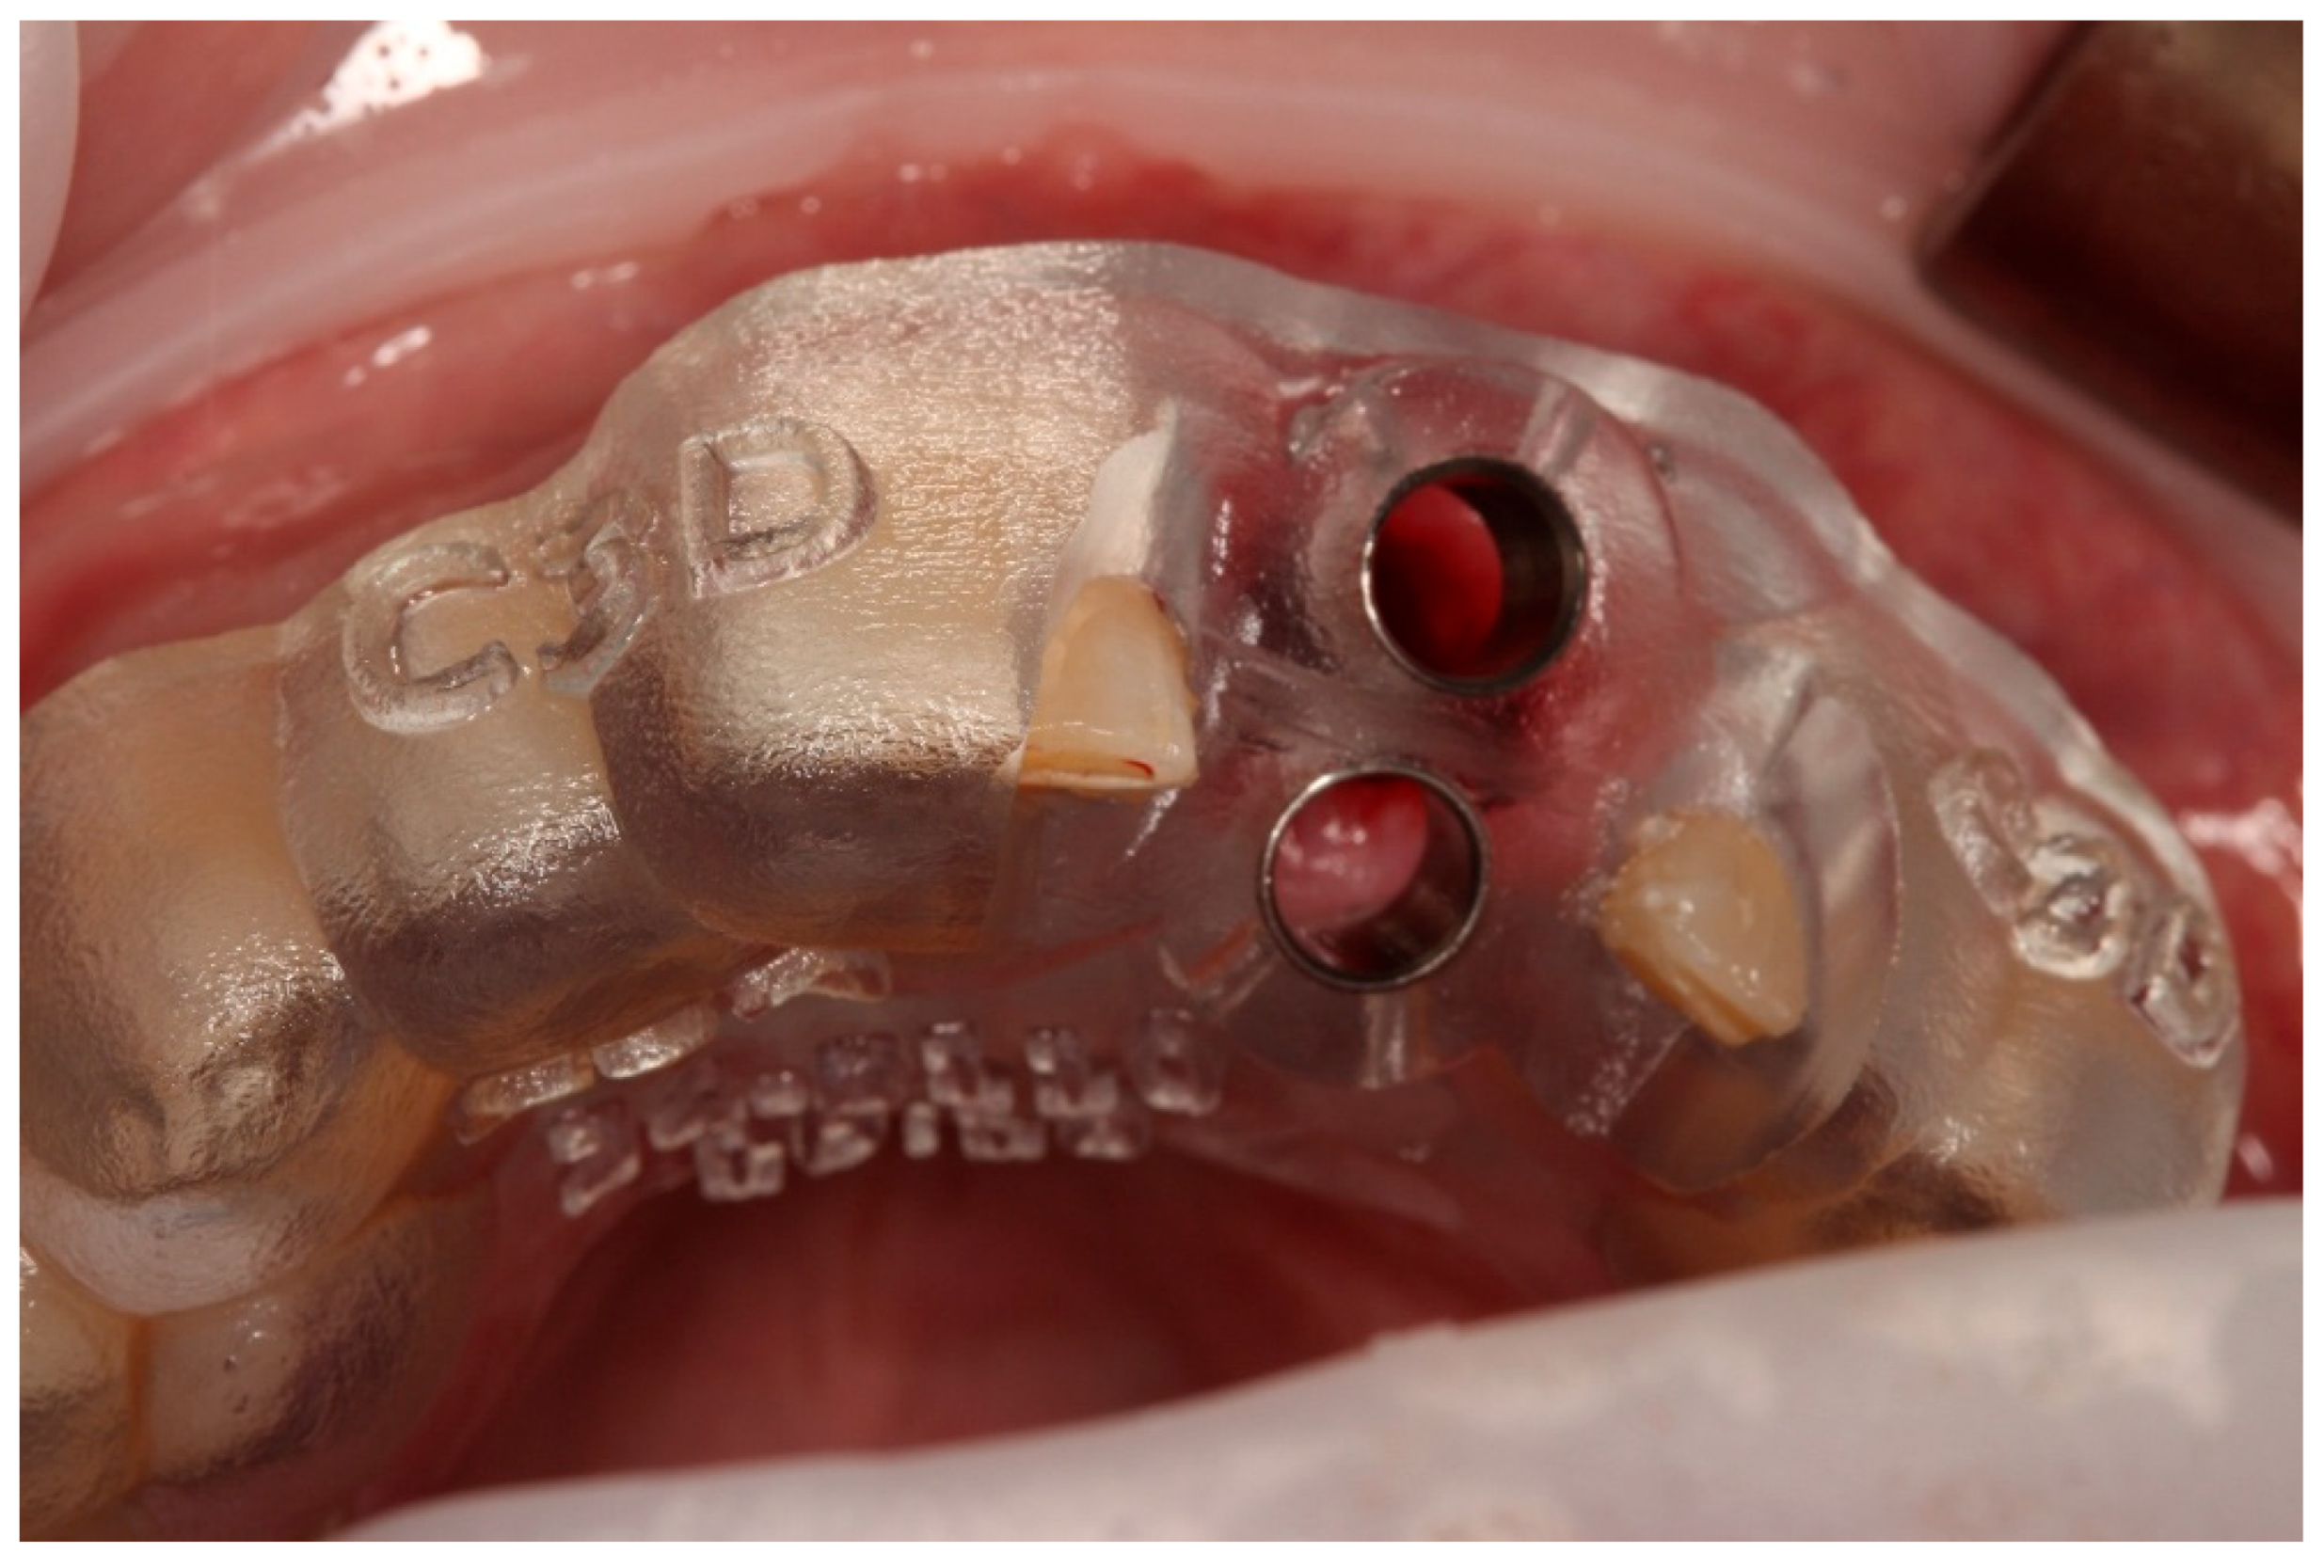

- Preparation of the recipient socket: After curettage of granulation tissue from the original socket, the CAD/CAM surgical guide was positioned. A guided osteotomy was performed using the implant-type drills from the C3D Cambados guided surgery kit, following the virtual plan. A biologic drilling protocol without irrigation was used to preserve autologous bone chips in the osteotomy walls. These chips were collected and later used as graft material. Drill sequence, diameters, and depth calibration followed the manufacturer’s recommendations and the digital plan, maintaining a stable trajectory and preserving palatal bone for primary stability.

- Verification with the 3D-printed replica: The printed tooth replica was inserted into the prepared socket to confirm angulation and depth prior to replantation of the original tooth.